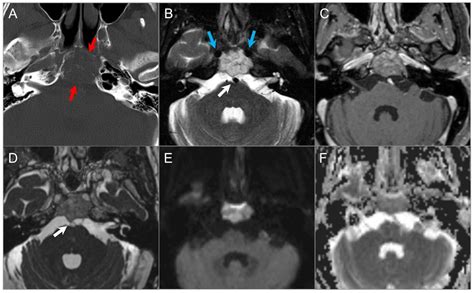

MRI (Magnetic Resonance Imaging) Provides high-resolution images of soft tissues, nerves, and the brain.

CT Scan (Computed Tomography) Highly effective at highlighting bony structures and identifying tumor-related bone erosion.